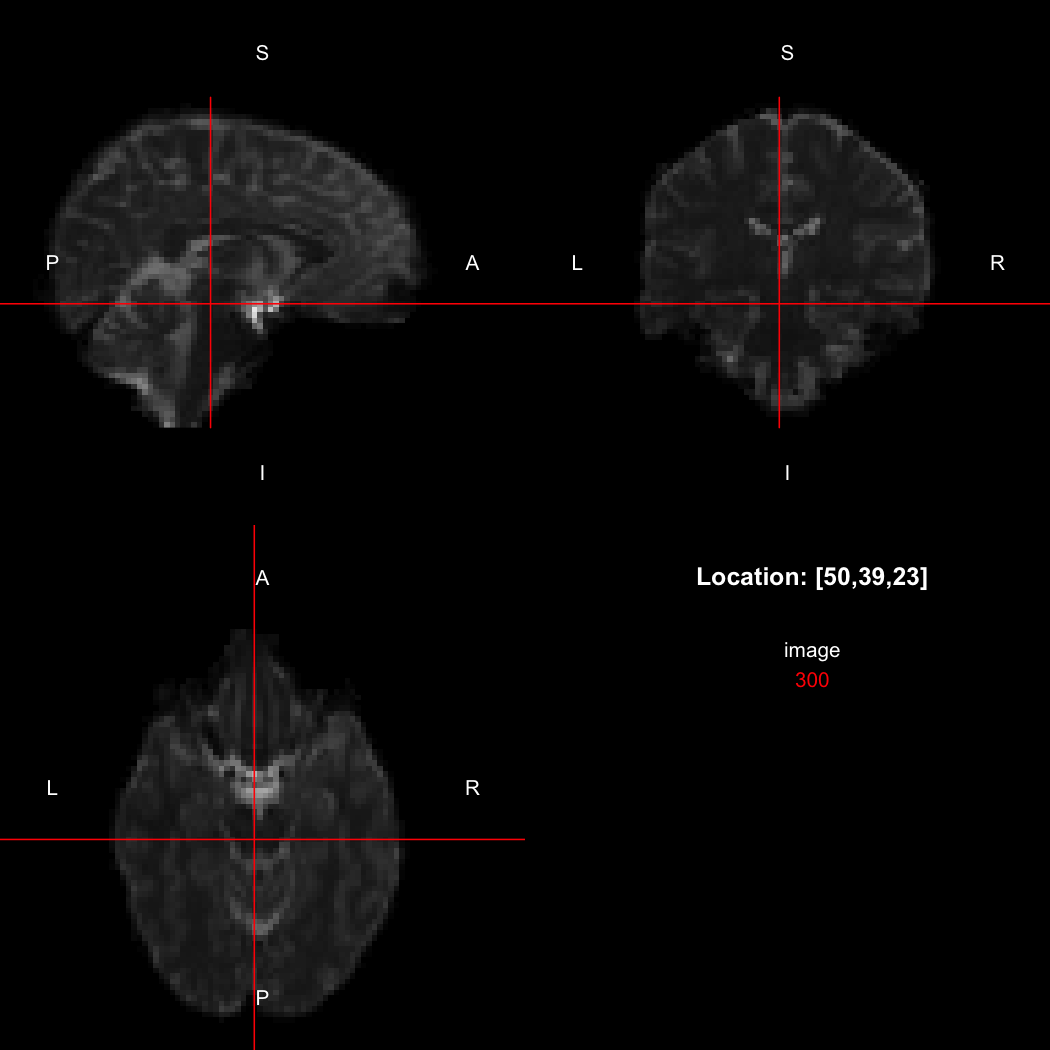

## [1] "LAS"So, here, “LAS” means that the positive x-axis points left, the positive y-axis anterior and the positive z-axis superior. This is the so-called “radiological” orientation convention, and can be requested when viewing images for those who are used to it:

view(image, radiological=TRUE)

Notice the left (L) and right (R) labels, relative to the view shown

above. Setting the radiologicalView option to

TRUE will make this the default for all future views.